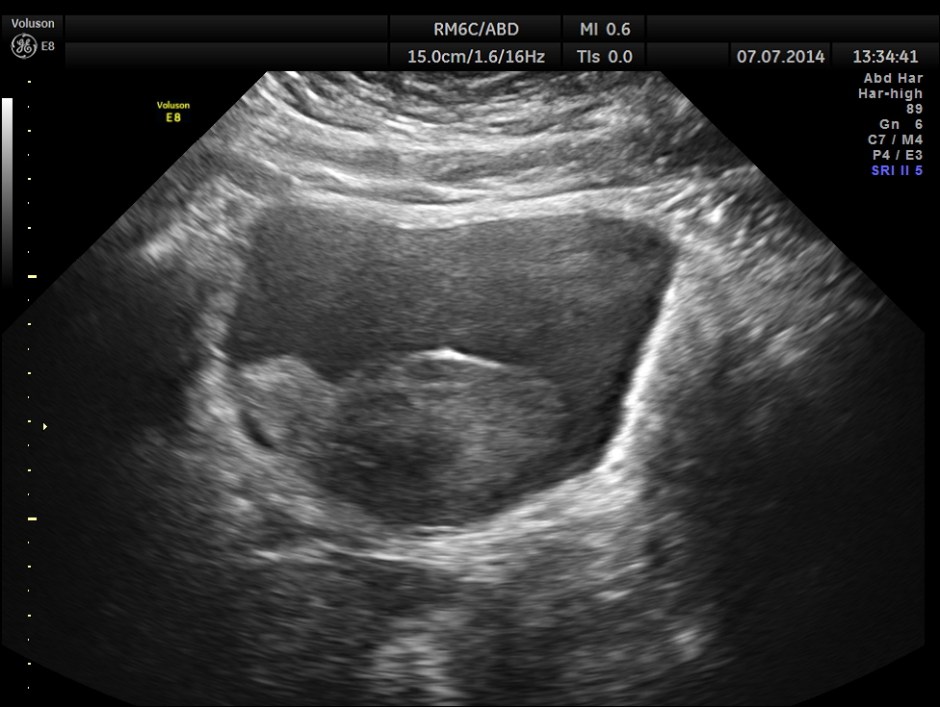

His ultrasound showed the following :

The urinary bladder showed ? mass lesion at first look.

With change of position this ” mass ” was seen to roll within the urinary bladder , suggestive of blood clot.

In this patient the increased vascularity is brought out very well by glass body imaging . Clots of blood seen in the urinary bladder gave the false impression of a mass lesion in the bladder initially.The importance of a dynamic study of turning the patient to the sides should always be remembered.